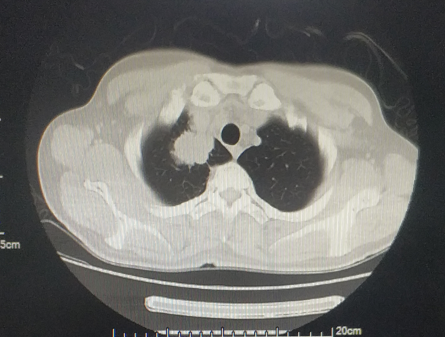

患者为46岁中年男性,主因前额搏动性疼痛1月余,加重1周至当地医院就诊,颅脑CT检查提示右侧颞顶叶占位:转移瘤?,入院完善相关术前检查后发现该患者肺部占位、颅内多发占位,怀疑肺癌脑转移瘤。 结合患者一般情况及影像学检查分析病情。认为颅内右侧颞顶叶肿瘤占位效应明显,导致中线移位,脑室受压,肿瘤进展较快,有进一步增大可能,严重时可能出现脑疝,危及生命。且该占位最大径>3cm,放化疗效果差,同时手术可明确肿瘤性质,因此计划手术切除右颞顶叶占位,其余颅内占位较小,占位效应不明显。肺部占位可在明确组织病理及分子病理后再行治疗。 颅脑磁共振提示颅内多发占位 胸部CT提示右上肺尖段占位 排除绝对手术禁忌后于2021年11月10日行全麻下左侧卧位右侧颞顶叶占位切除术。术后患者病情平稳,未见新发神经功能障碍,查体同术前。术后病理提示:符合低分化腺癌,考虑为肺来源。免疫组化提示:CK7(+)、NapsinA(+)、TTF-1(+)、ALK(ventana)(-)、PD-L1(SP263)(30%)。分子病理提示:EGFR 19缺失突变。 术区CT 出院后患者至我院脑转移瘤多学科联合门诊拟定下一步诊疗方案。脑转移瘤MDT专家团队联合为转移瘤患者会诊,各学科专家详细询问了患者的相关病情及诊疗经过,并仔细阅读了影像学检查及实验室检验结果,从各自专业角度,结合患者整体病情,提出了各自相关专业的处理方案以及为患者制定了全面、精准、规范的诊疗计划: 神经外科冯世宇主任:患者脑转移瘤术后恢复良好,建议下一步综合治疗。 放射科肖华锋主任:阅患者术前MRI和术后CT提示颅内多发转移瘤,右侧颞顶叶转移瘤术后改变。肺部CT提示右上肺肺癌,建议肺部CT增强扫描,颅脑MR增强扫描,定期复查。 胸外科马永富主任:病史已阅,建议完善胸部增强CT。评价右上肺手术机会。 肿瘤内科吴志勇主任:肺癌脑转移考虑EGFR作为主要驱动基因治疗,结合TP53/ target=_blank class=infotextkey>P53突变,建议应用EGFT TKI+安罗替尼治疗,EGFT TKI首选奥希替尼。 综合意见: 患者就诊联合门诊后积极行化学药物治疗(奥希替尼,口服 80mg 1/日;安罗替尼 口服 8mg 1/日),近日再次至我院复查颅脑磁共振提示病情控制良好(如图)。 右颞顶占位 其余多发占位 肺部占位 病例总结 该患者为46岁中年男性,主因头部疼痛发现颅内多发及肺部占位,高度怀疑肺癌脑转移,但肿瘤性质未明确;颅内右侧颞顶叶肿瘤占位效应明显;肿瘤直径>3cm,放化疗治疗效果较差并且存在风险。手术可快速解除颅内高压症状,消除病灶对周围脑组织的压迫,并且明确肿瘤性质,根据组织病理及分子病理能够寻找肿瘤相关突变基因靶点药物。因此采取了手术切除颅内右侧颞顶叶肿瘤,缓解了占位效应,明确了肿瘤组织病理及分子病理,为患者赢得了下一步综合治疗的时间。 该病例的启示 颅内转移瘤是否手术应进行综合评估,其中包括肿瘤的数量、大小、性质、部位、患者一般情况等。 1、 颅内单发肿瘤最大径>3cm,水肿范围大、占位效应明显时应行手术切除,及时进行减压,挽救患者生命;但其病理性质明确,且对放化疗敏感时,可不首选手术治疗。 2、 颅内多发,若肿瘤数目≤3个,且能完全切除者可行手术治疗;若肿瘤>3个,则建议行放疗、化疗等非手术治疗。但是若占位效应明显、出现梗阻性脑积水、肿瘤卒中甚至脑疝等情况时应行手术切除较大占位病变以达到减压目的,患者赢得下一步治疗的时间以后,再根据组织病理和分子病理,进行化疗或靶向治疗或者放疗等综合治疗。 3、 若肿瘤性质不明确者,应行手术切除或穿刺活检明确组织病理及分子病理,根据其结果可寻找有效的化疗药物或靶向药物等综合治疗的方案。 4、 肿瘤部位较深或位于功能区(如脑干、基底节区、丘脑),评估手术风险高可能带来不可逆的功能障碍,一般不首选手术,可先选择放疗或化疗。 解放军总医院第一医学中心脑转移瘤联合会诊团队由神经外科、肿瘤科、放疗科、放射科、胸外科、乳腺外科等科室专家组成的专家团队,各相关学科专家结合患者的具体情况,制定出最合适患者的个性化的精准治疗方案,提高患者的治疗效果、生活质量以及生存时间。简要病史

术前影像